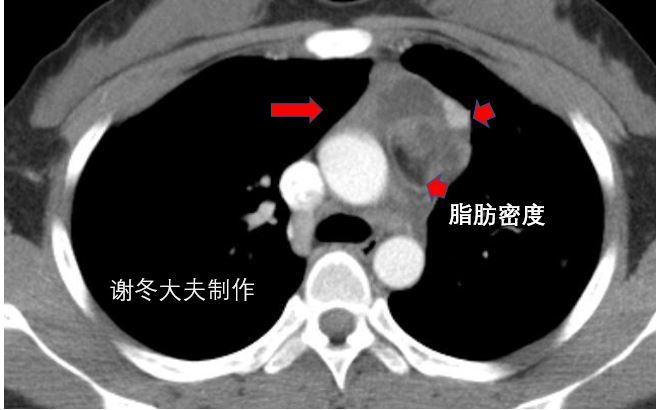

4.谢大夫,这个前纵隔占位,是胸腺瘤吗?

回答:这是一个纵隔畸胎瘤,不是胸腺瘤,这个肿瘤内部包含很多脂肪成分,以及钙化影,这些都是典型纵隔畸胎瘤的表现